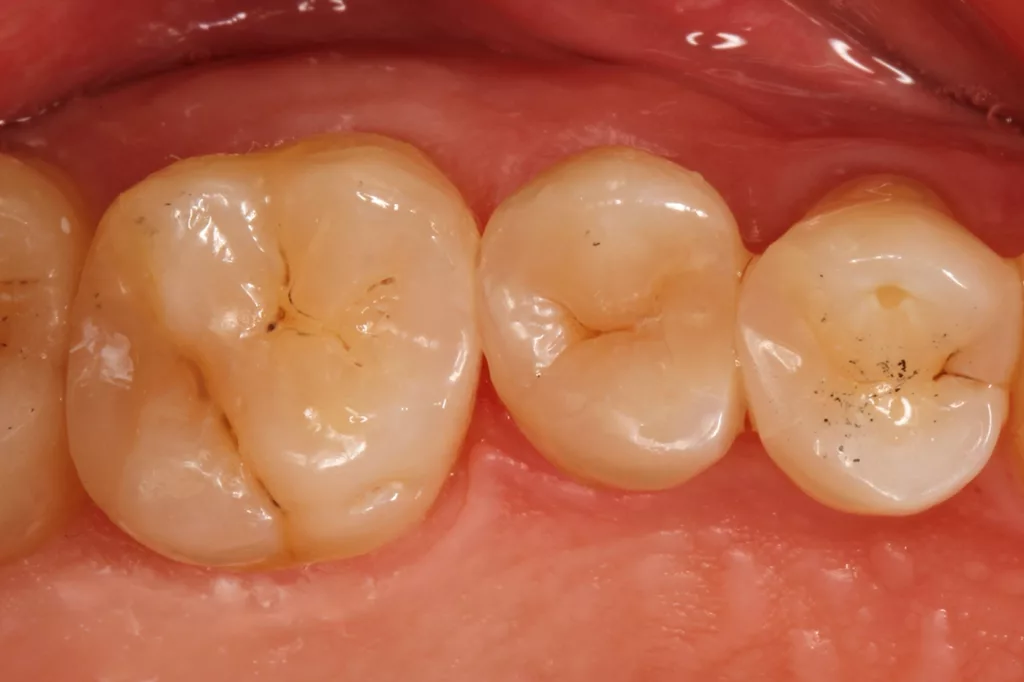

Fall 5: Versorgung einer okklusalen Kavität an einem unteren Molaren

Auch im Molarenbereich können Bulkflow-Materialien effektiv und ökonomisch eingesetzt werden, ohne Abstriche an der Ästhetik machen zu müssen, was der Fall des hier versorgten Zahnes 46 bei einer 22-jährigen Patientin zeigt. Die Abbildung 24 stellt die bereits präparierte und mit einem Einzelzahnkofferdam isolierte Kavität mit der Phosphorsäurekonditionierung der Schmelzränder (Gel Etchant, Kerr) dar. Die Entscheidung zur absoluten Trockenlegung fiel aufgrund der nicht so einfach kontrollierbaren Zunge und der vielen Schluckreflexe, was das Risiko einer ungewollten Speichelkontamination der Klebefläche unverhältnismäßig erhöhte.

Die Verwendung des Kofferdams ist generell eine sehr empfehlenswerte, aber keine zwingende Voraussetzung zur Etablierung einer suffizienten Kontaminationskontrolle [47,96]. Das bisher auch bereits verwendete Zwei-Schritt-Universaladhäsiv G2 Universal wurde hier in der selektiven Schmelzätztechnik angewendet, d.h., das Material arbeitet auf dem Dentin selbstkonditionierend (Abb. 25). Die bislang zu diesem innovativen Mehrflaschen-Universaladhäsiv publizierten Daten zeigen eine beeindruckende Performance, die den Vergleich mit sogenannten Goldstandards [98] wie einem Optibond FL nicht scheuen müssen [13,18,34,58,63,114,119,127,130]. Im nächsten Schritt wurden die einzelnen Höcker mit dem angenehm standfesten Flowable aufgebaut (Abb. 26). Die Abbildung 27 zeigt die komplett versorgte okklusale Kavität, die Abbildung 28 die Situation unmittelbar nach Ausarbeitung und Politur. Erneut beeindruckt die gute Farbadaptation.